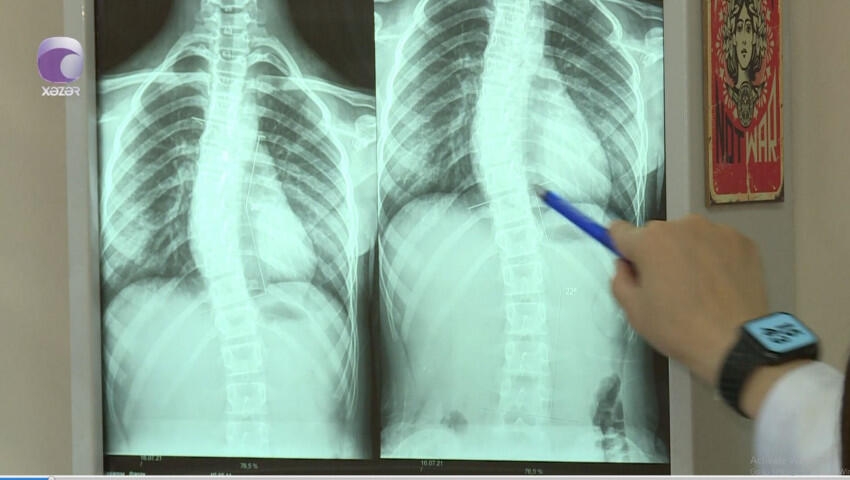

"Son zamanlar 8-12 yaş aralığındakı uşaqlarda bel və boyun ağrıları ilə bağlı şikayətlər nəzərəçarpacaq dərəcədə artıb.

Halbuki, illər öncə uşaqlarda belə problemlər olmurdu. Bunu fizioterapevt Səidə Kərimova "Xəzər xəbər"ə müsahibəsində deyib.

Sonxeber.net xəbər verir ki, həkim səbəb olaraq bildirdi ki, uşaqların çantaları kifayət qədər ağırdır. Çiyin ağrıları isə xüsusən ona görə yaranır ki, ağır çantaları daşıyarkən, kəmərləri uşağın yumşaq toxumasını sıxıb kəsir.

Həkim bildirdi ki, bu yaşda uşaqlar oturanda, xüsusilə də dərs oxuyarkən, qamətini dik tutmalıdır.